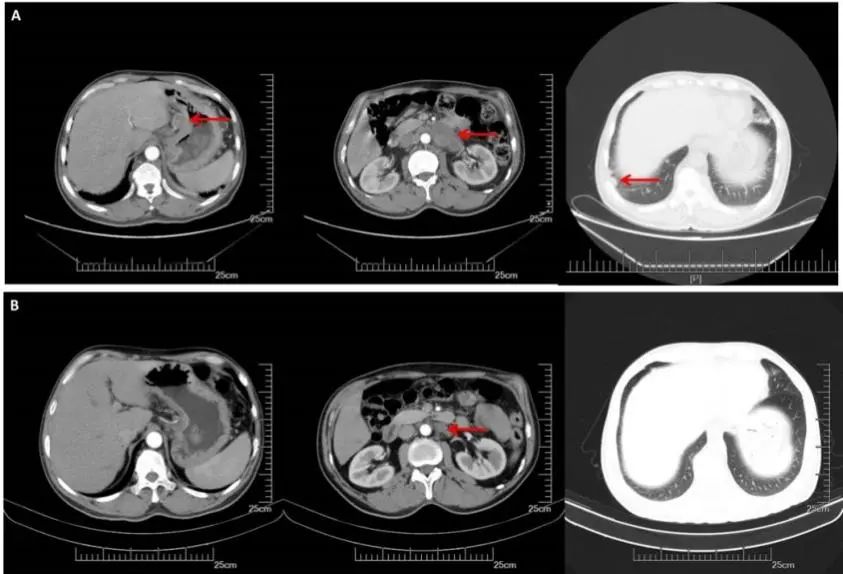

CT(2017.9.29):1、胃癌术后改变,吻合口增厚,较前减轻。腹膜后可见多发增大淋巴结影。右侧锁骨上、双侧膈肌脚后及纵隔内见多发淋巴结,部分较前增大,双肺散在小结节,较前变化不大。

CT(2018.3.27):胃癌术后改变,吻合口增厚,较前减轻。腹膜后可见多发增大淋巴结影,较前缩小。右侧锁骨上、双侧膈肌脚后及纵隔内见多发淋巴结,部分较前增大。双肺散在小结节,较前变化不大。

疗效评价:PD

A:CT增强(2017.09.29):右锁骨上,纵膈,腹腔淋巴结明显增大,双肺无明显变化;B:CT增强(2018.03.27):腹膜后多发增大淋巴结较前缩小,右侧锁骨上纵隔内见多发淋巴结,部分较前增大,双肺较前变化不大。